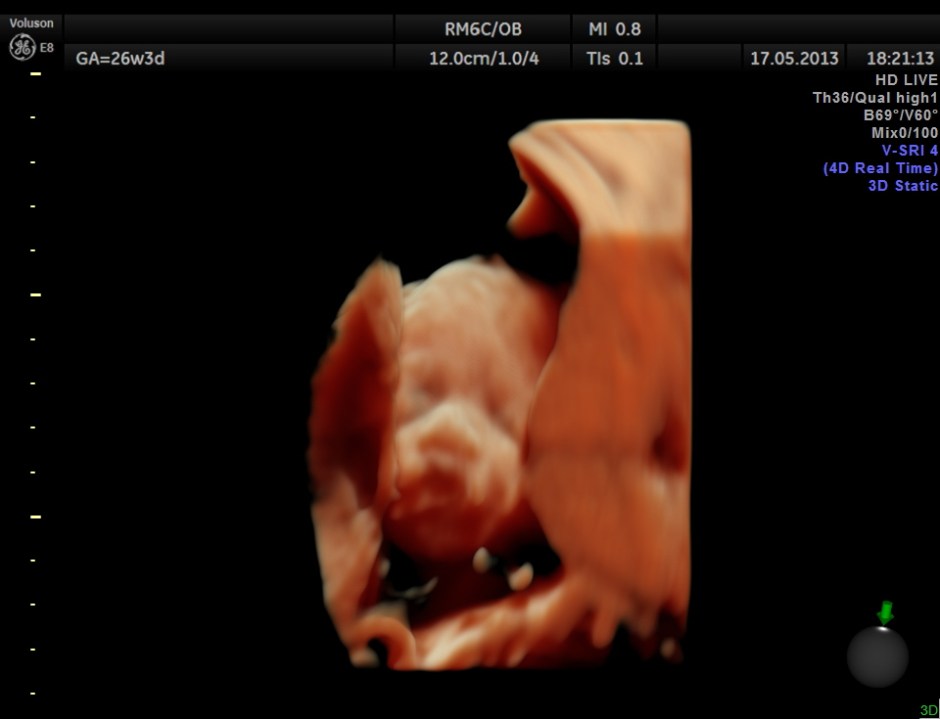

The following are 3 D reconstructed sagittal and coronal images .

The following images show the face and the palate.